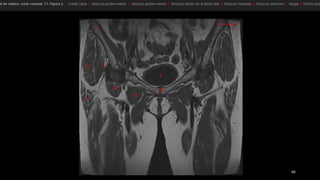

• músculo glúteo mayor (GMa)

• músculo tensor de la fascia lata (Tfl anterior y la

fascia lata (FL) situada entre ambos músculos

• «bandeleta de Massiat» (BM)

• glúteo medio (GMe) y glúteo menor (GMI)

• trocánter mayor (TM)

• El músculo glúteo mayor (GMa).

• músculos semimembranoso (sm), semitendinoso (st)

y la cabeza larga del bíceps femoral (elb).

• músculo semimembranoso tiene su propio tendón

(1).

• semitendinoso y la cabeza larga del bíceps se originan

en la cara lateral de la tuberosidad isquiática -en un

tendón común (2).

• nervio ciático (NC). TM, trocánter mayor.

• Glúteo mayor (GMa)

• Glúteo medio (GMe)

• Glúteo menor (GMi)

• Fascia lata (FL)

• Tendón del glúteo menor (1)

• Aanterior del tendón del glúteo

medio (2)

• Posterior del tendón del glúteo

medio (3)

• TM, trocánter mayor

• Tm, trocánter menor.

• músculo glúteomayor (GMa) • músculo tensor de la fascia lata (Tfl anterior y la fascia lata (FL) situada entre ambos músculos • «bandeleta de Massiat» (BM) • glúteo medio (GMe) y glúteo menor (GMI) • trocánter mayor (TM)

• El músculoglúteo mayor (GMa). • músculos semimembranoso (sm), semitendinoso (st) y la cabeza larga del bíceps femoral (elb). • músculo semimembranoso tiene su propio tendón (1). • semitendinoso y la cabeza larga del bíceps se originan en la cara lateral de la tuberosidad isquiática -en un tendón común (2). • nervio ciático (NC). TM, trocánter mayor.

• Glúteo mayor(GMa) • Glúteo medio (GMe) • Glúteo menor (GMi) • Fascia lata (FL) • Tendón del glúteo menor (1) • Aanterior del tendón del glúteo medio (2) • Posterior del tendón del glúteo medio (3) • TM, trocánter mayor • Tm, trocánter menor.